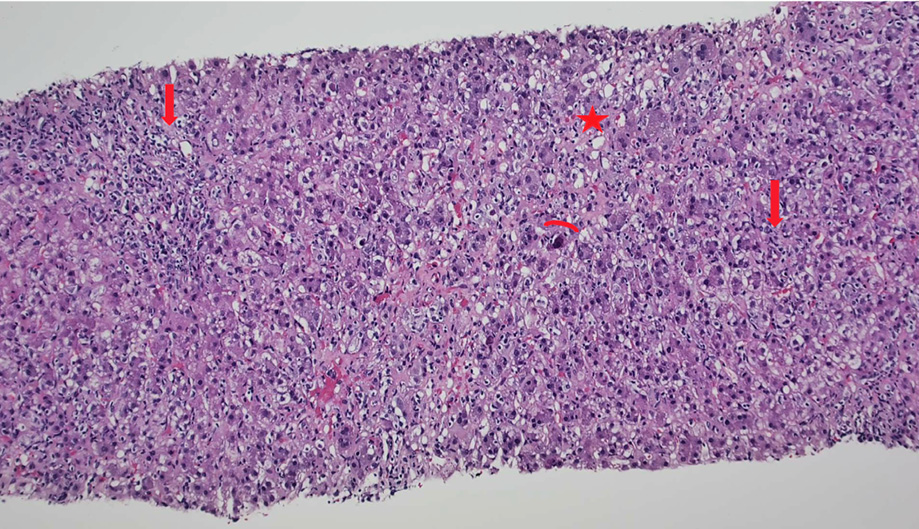

Ultrasound of the liver showed coarse echotexture and patent portal and hepatic veins. Liver biopsy showed diffuse steatosis both macro and microvascular. There was a marked expansion of the portal areas along with moderate infiltration of lymphocytes, histiocytes, eosinophils, neutrophils, and occasional plasma cells. There was moderate interface inflammation in all the portal tracts. Lobular inflammation with neuroinflammatory foci was noted along with apoptotic hepatocytes, giant cell transformation, and ballooning of the hepatocyte. Also mid-focal bile duct injury was seen [Figures 1 and 2].

Figure 1: Sections of the liver showing disarray of the architecture with the portal and lobular inflammation (arrows), apoptosis (arch), and steatosis (star) (hematoxylin and eosin staining, magnification = 10 ×).